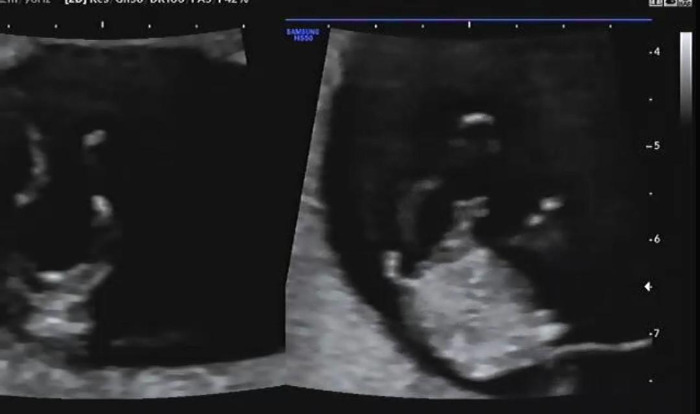

4주 만에 보는 햇님(태명)이는 젤리 곰 형태에서 사람의 형태로 바뀌었다. 완전한 사람의 형태는 아니지만 이제는 정말 내가 아기를 품에 안고 있다는 생각이 들었다. 한 달 만에 보는 아기는 제법 성장해서 얼굴에 눈코입 윤곽이 보이는데 너무나 신기했다. 나에게는 고작 4주였지만 아기에게는 엄청난 성장을 보여주는 기간이 되었다. 젤리 곰 마냥 짧고 동그랗게만 보이던 팔다리는 어느새 길어져 이리저리 휘젓고 있는 아기를 보니 또 감동을 받았다.

초음파를 확인하고 나면 기형아 검사를 위해 혈액검사를 시행한다. 기형아 검사는 총 2회로 진행되며 혈액검사와 태아 목 투명대를 측정하여 기형아 위험도를 검사한다. 1차 기형아 검사는 일반적으로 10~14주 사이에 많이 진행된다. 2차례 모두 진행이 끝나면 결과를 확인할 수 있는데 수치가 이상이 있다면 양수검사까지 진행을 하게 된다. 2회로 진행되는 기형아 검사는 100%의 정확도가 아닌 80~85% 정확도를 가지고 있으며 1차에서 이상소견이 발견되더라도 2차에는 정상 소견을 받는 사람도 많이 있다고 한다.

태아 목 투명대를 측정하여 다운증후군을 미리 예측할 수 있는데 다행히 나는 정상 수치라서 다음 초음파와 혈액검사 상 모두 정상이라면 크게 걱정할 필요가 없다는 이야기를 들었다. 목 투명대는 주수마다 정상 길이 범위가 다르며 보통 3mm 이상은 혈액검사뿐 아니라 양수검사를 시행한다.